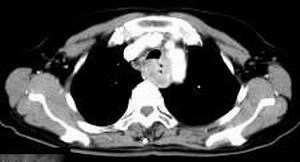

女,61岁,吞咽困难(包括开水)已久。

食道中上段癌并锁骨上窝淋巴结转移.

1、同意食道上段ca併淋巴结转移。

2、做食道呑钡就一目了然。

3、右侧甲状腺是否有问题?是否甲状腺ca转移食道上段。因为肿块顶部图像没有,请楼主展示,谢谢!

食道中上段中分化鳞癌伴锁骨上淋巴结转移

大家都很正确,谢谢!